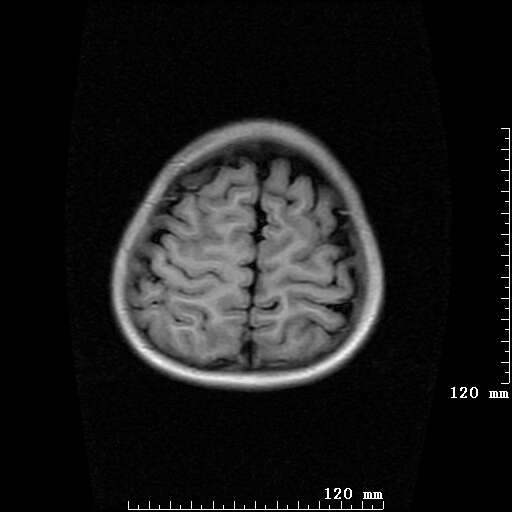

女,7岁,三岁才说话、走路。现智力尚可,走路不稳。临床怀疑大脑发育不全。

考虑 脑白质发育不良

脑折质变薄,双侧侧脑室稍扩张,支持考虑脑折质发育不良

考虑胼胝体发育不全,髓鞘形成不良。

支持考虑胼胝体发育不全,髓鞘形成不良。

侧脑室周围白质数量减少,侧脑室不对称性扩大,左侧侧脑室后角呈方形改变,脑沟加深,结合临床考虑脑室周围白质软化症(pvl)。期待结果!

支持脑白质发育不良。